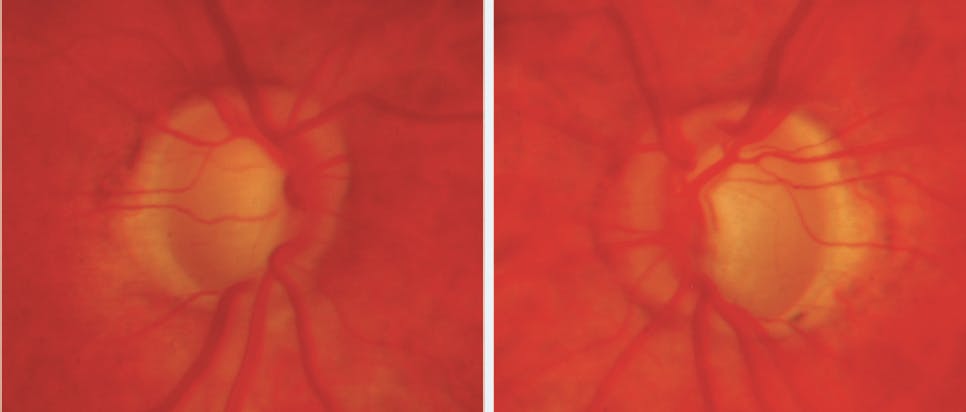

- By 2016 the glaucoma in her left eye had worsened despite maximum medical therapy. On examination, IOP in the left eye was 18 mm Hg and imaging confirmed advanced glaucomatous damage in both eyes, with the left eye demonstrating more severe damage (Figures 1 and 2).